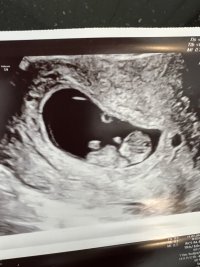

Netopp vært på ultralyd og oppfølging på sykehuset , blir tettere oppfølging nå og jeg kan bare ringe og kome om det er noe.ikke tegn til noe mer blødning nå , sannsynligvis har det blødd ut men alikevel var de ikke helt sikker..men såg bra ut. Lille sprella og hjerte slo. Alt bare fint. Har litt veske i buken og cyster etter ivf stimulering som de også vil følge ekstra opp.. veldig flink og hyggelig lege . Og veldig gla alt sto så bra til. ❤️❤️og at helsevesenet funker så blir ekstra ultralyder dær også.